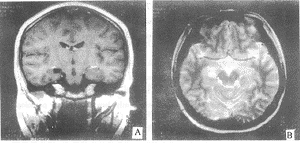

图1 右侧颞窝蛛网膜囊肿,同侧海马较小,T2加权像示海马信号较高,手术、病理证实为海马硬化

图2 右侧环池(脉络裂)蛛网膜囊肿,海马受压,T2加权像信号较高,手术、病理正视为海马硬化

1例蛛网膜囊肿位于右颞窝病人(图1)、1例位于环池病人(图2)及1例位于颞角病人脑电图提示有癫痫波,以颞叶癫痫做前颞叶切除术,术中见海马结构及部分颞叶皮层有异常波或癫痫波,病理均提示颞叶皮层和海马结构胶质增生。1例额部(图3A)及1例顶区蛛网膜囊肿(图3B)病人做囊肿切除术,术中见病灶周围异常波。所有手术病人术后短期随访4例无癫痫发作,1例发作减少。

临床上常可见癫痫病人有蛛网膜囊肿而无其它脑实质病变,文献报告蛛网膜囊肿并发癫痫的发病率不等,Arroyo[2]发现1.9%的癫痫病人有蛛网膜囊肿,Morioka[3]也发现56例中颅窝蛛网膜囊肿病人中11例(19%)有癫痫病史,发病率与本组(22.9%)相似。也有文献报告[3]异常脑电波与囊肿位置、大小无关,认为颅中窝蛛网膜囊肿的占位效应不可能是癫痫发作的原因。那么两者到底有没有关系呢?本组30例癫痫病人中17例有脑电图资料,3例病人有明确的颞区癫痫波,MRI示海马体积缩小,T2加权像海马信号增高,为海马硬化的表现[1],并手术证实,另1例额部和1例顶部蛛网膜囊肿病人术中见病灶周围也有异常脑电波,可以说这5例异常脑电波与蛛网膜囊肿所在部位基本一致,但12例发作间期脑电图仅见异常脑电波无明确定位或定侧。众所周知颅内其他类型癫痫病理灶也可以在该病灶中、边缘或较远的部位形成致痫灶,颅内常见的肿瘤性病灶,有35%发生继发性癫痫[4],所以我们认为蛛网膜囊肿和颅内其他病灶一样也可以引起继发性癫痫发作,甚至形成颞叶癫痫。